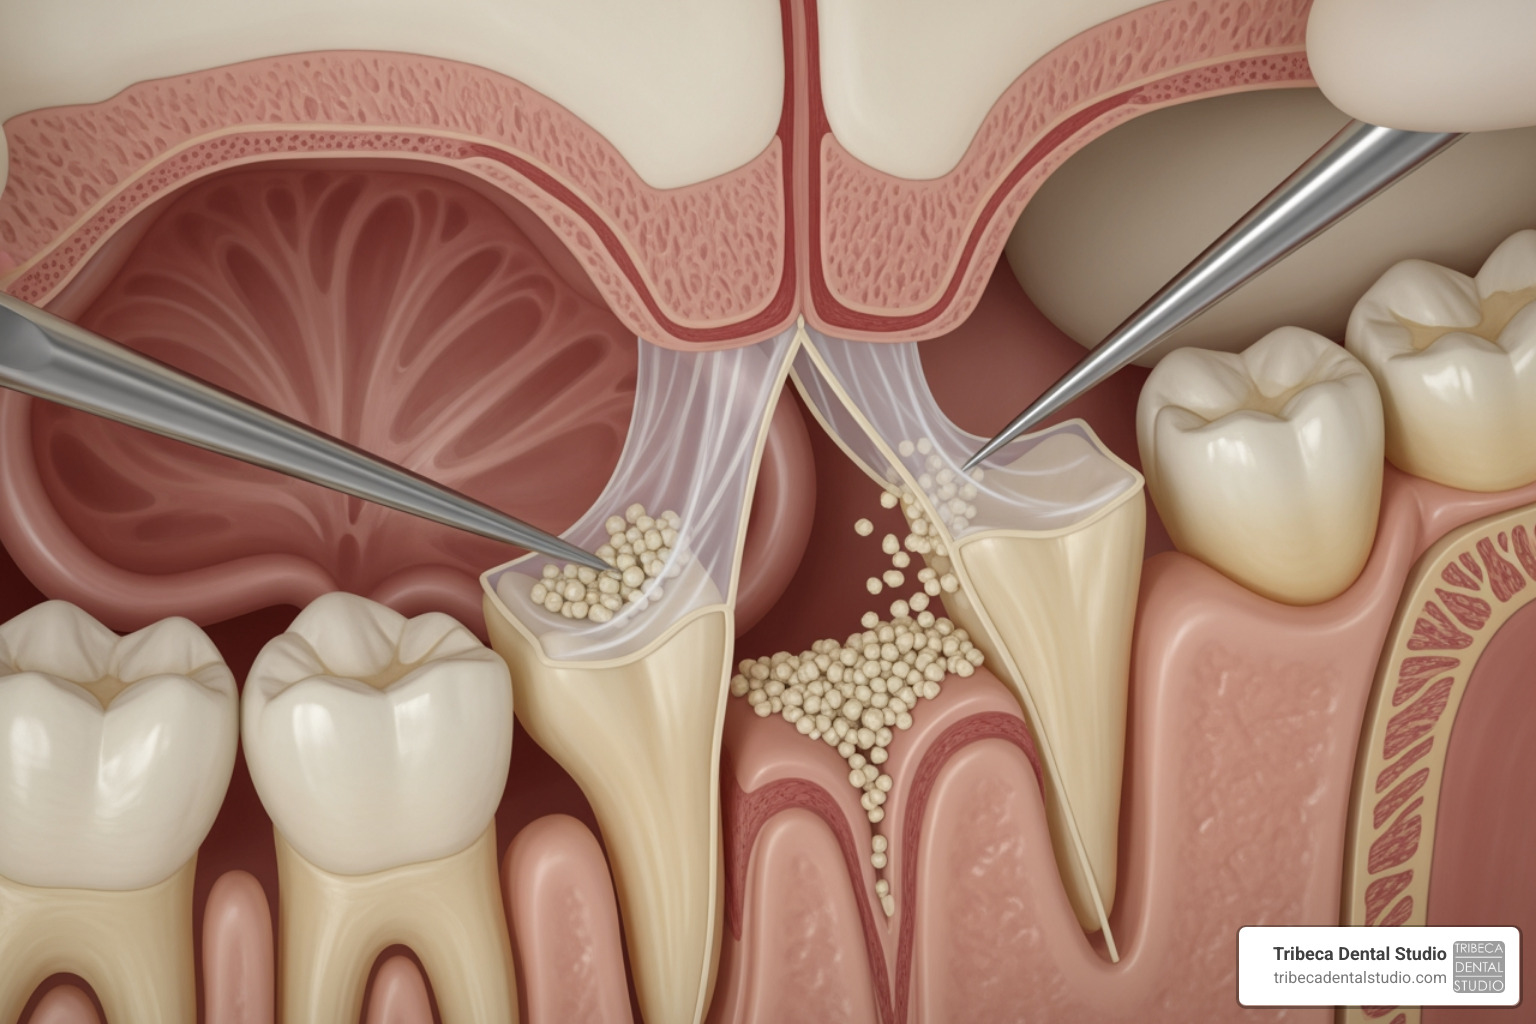

- Incision Creation: After administering local anesthesia, a small incision is made in the gum tissue to expose the bone.

- Creating Access: A small opening is made in the bone—either a lateral “window” or directly through the implant site for a crestal approach.

- Gently Lifting the Schneiderian Membrane: The thin membrane lining the sinus is carefully lifted. Our specialists use advanced microsurgery techniques for greater precision, which reduces the risk of perforation and leads to less post-operative pain and swelling.

- Placing Bone Graft Material: The newly created space is filled with bone graft material, which acts as a scaffold for new bone growth.

- Suturing the Site: The gum tissue is sutured back into place to protect the graft and promote healing.